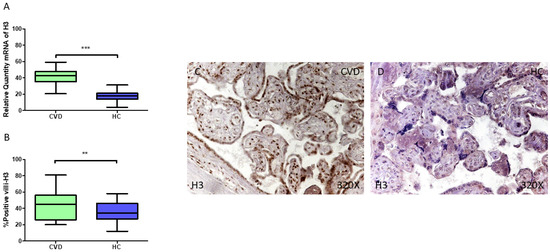

3.1. Placentas of Women Who Undergo Chronic Venous Disease During Pregnancy Display Decreased Expression of Key Circadian Markers

3.2. The Placentas of Women with Chronic Venous Disease During Pregnancy Show Evidence of Altered Epigenetic Markers